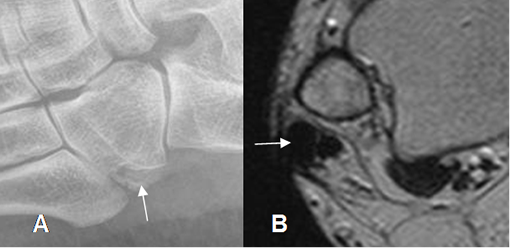

Fig 70. Tendinitis crónica de peroneos.

A: Rx oblicua del pie. Calcificación de la parte distal del peroneo corto, antes de su inserción.

B: RM axial en T2. Engrosamiento del tendón peroneo largo, por inflamación crónica.